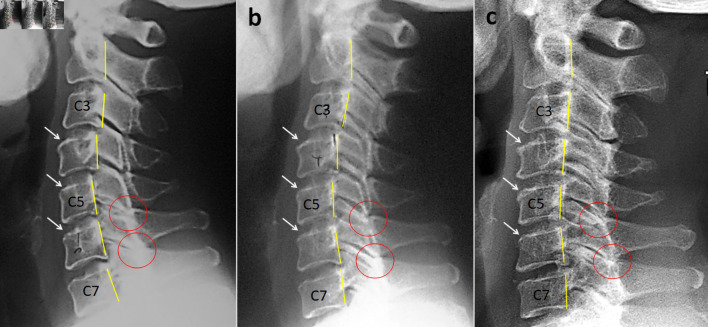

Figure 1

Cervical radiography revealed posterior slippage of C3 on C4 and C4 on C5, with sclerosis over the upper endplate of the C4, C5, and C6 vertebrae (Figure 1a). Disc space narrowing was not significant in the cervical spine. Other pathologies (e.g., fracture, cancer, and infection) were excluded on radiography. The patient was diagnosed with right C5 radiculopathy associated with degenerative spondylolisthesis.

The patient occasionally experienced episodes of mild neck pain, which subsided promptly after additional manual care. The radiographs obtained at the 4–year follow-up in 2013 demonstrated improvement in cervical slippage at all levels (Fig. 1b). Following 13 years of chiropractic MC, cervical radiographs taken in 2022 revealed restoration of cervical alignment (Fig. 1c). The rate of missed appointment was less than 10%. Regarding the home exercise, an approximate rate of 45% patient adherence was achieved across the entire MC program based on patient self-monitoring. Additional effects of the succeeding home exercises might also potentially have a role to play in better rehabilitation outcomes of her neck complaints. No other pathological conditions or treatment-related adverse events were reported. For a summary timeline events, please see Figure 2.

With regard to this case, the patient underwent monthly MC for 13 years. As her cervical alignment continued to improve during the maintenance period (Fig. 1), the MC prominently exhibited a potential effectiveness for this patient. A personalized MC can be viewed as a form of preventive visit after the initial treatment for recurrent or episodic pain and musculoskeletal dysfunction. [9] The prevention of further episodes (secondary prevention) and associated sequelae (tertiary prevention) is equally important. [21] The MC strategy required only a slightly higher number of chiropractor visits and should be considered an adjuvant treatment option for patients with recurrent or persistent spinal pain who respond well to the initial course of chiropractic care. [9]